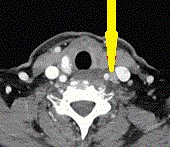

Contrast-enhanced CT demonstrates soft-tissue lesion in left carotid sheath (Courtesy Dr. V. Penopoulos)